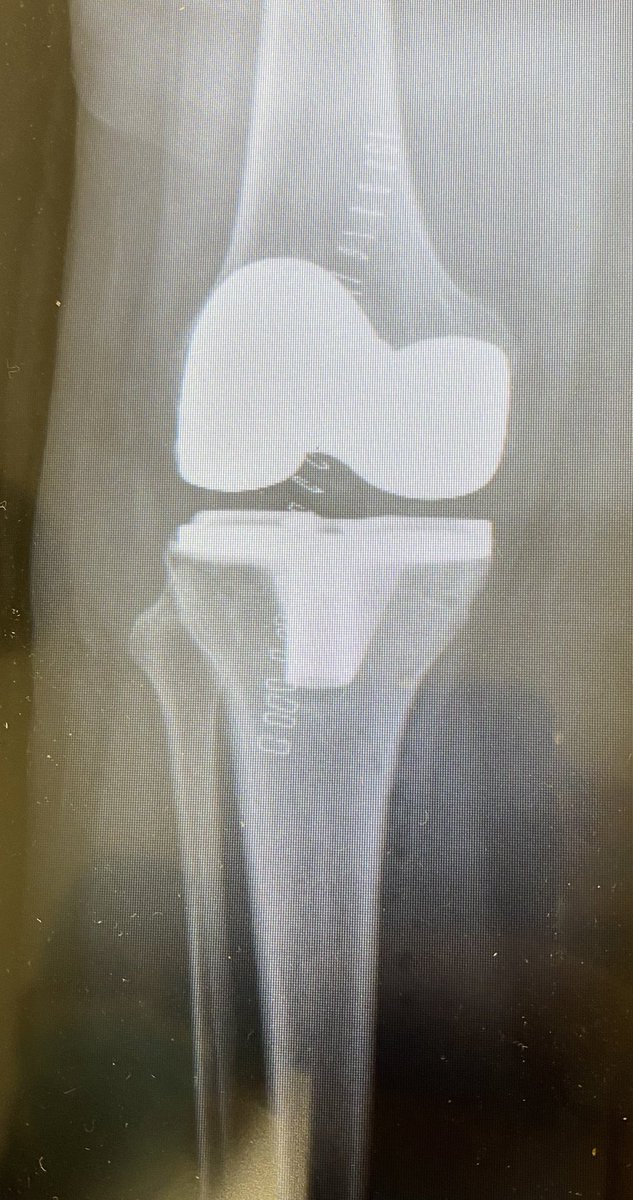

حيث يكون مبدئها استبدال او تلبيس مفصل الركبة بمفصل صناعي

حيث تكون نتائجها مرضية و ممتازة اذا أجريت للمريض المناسب